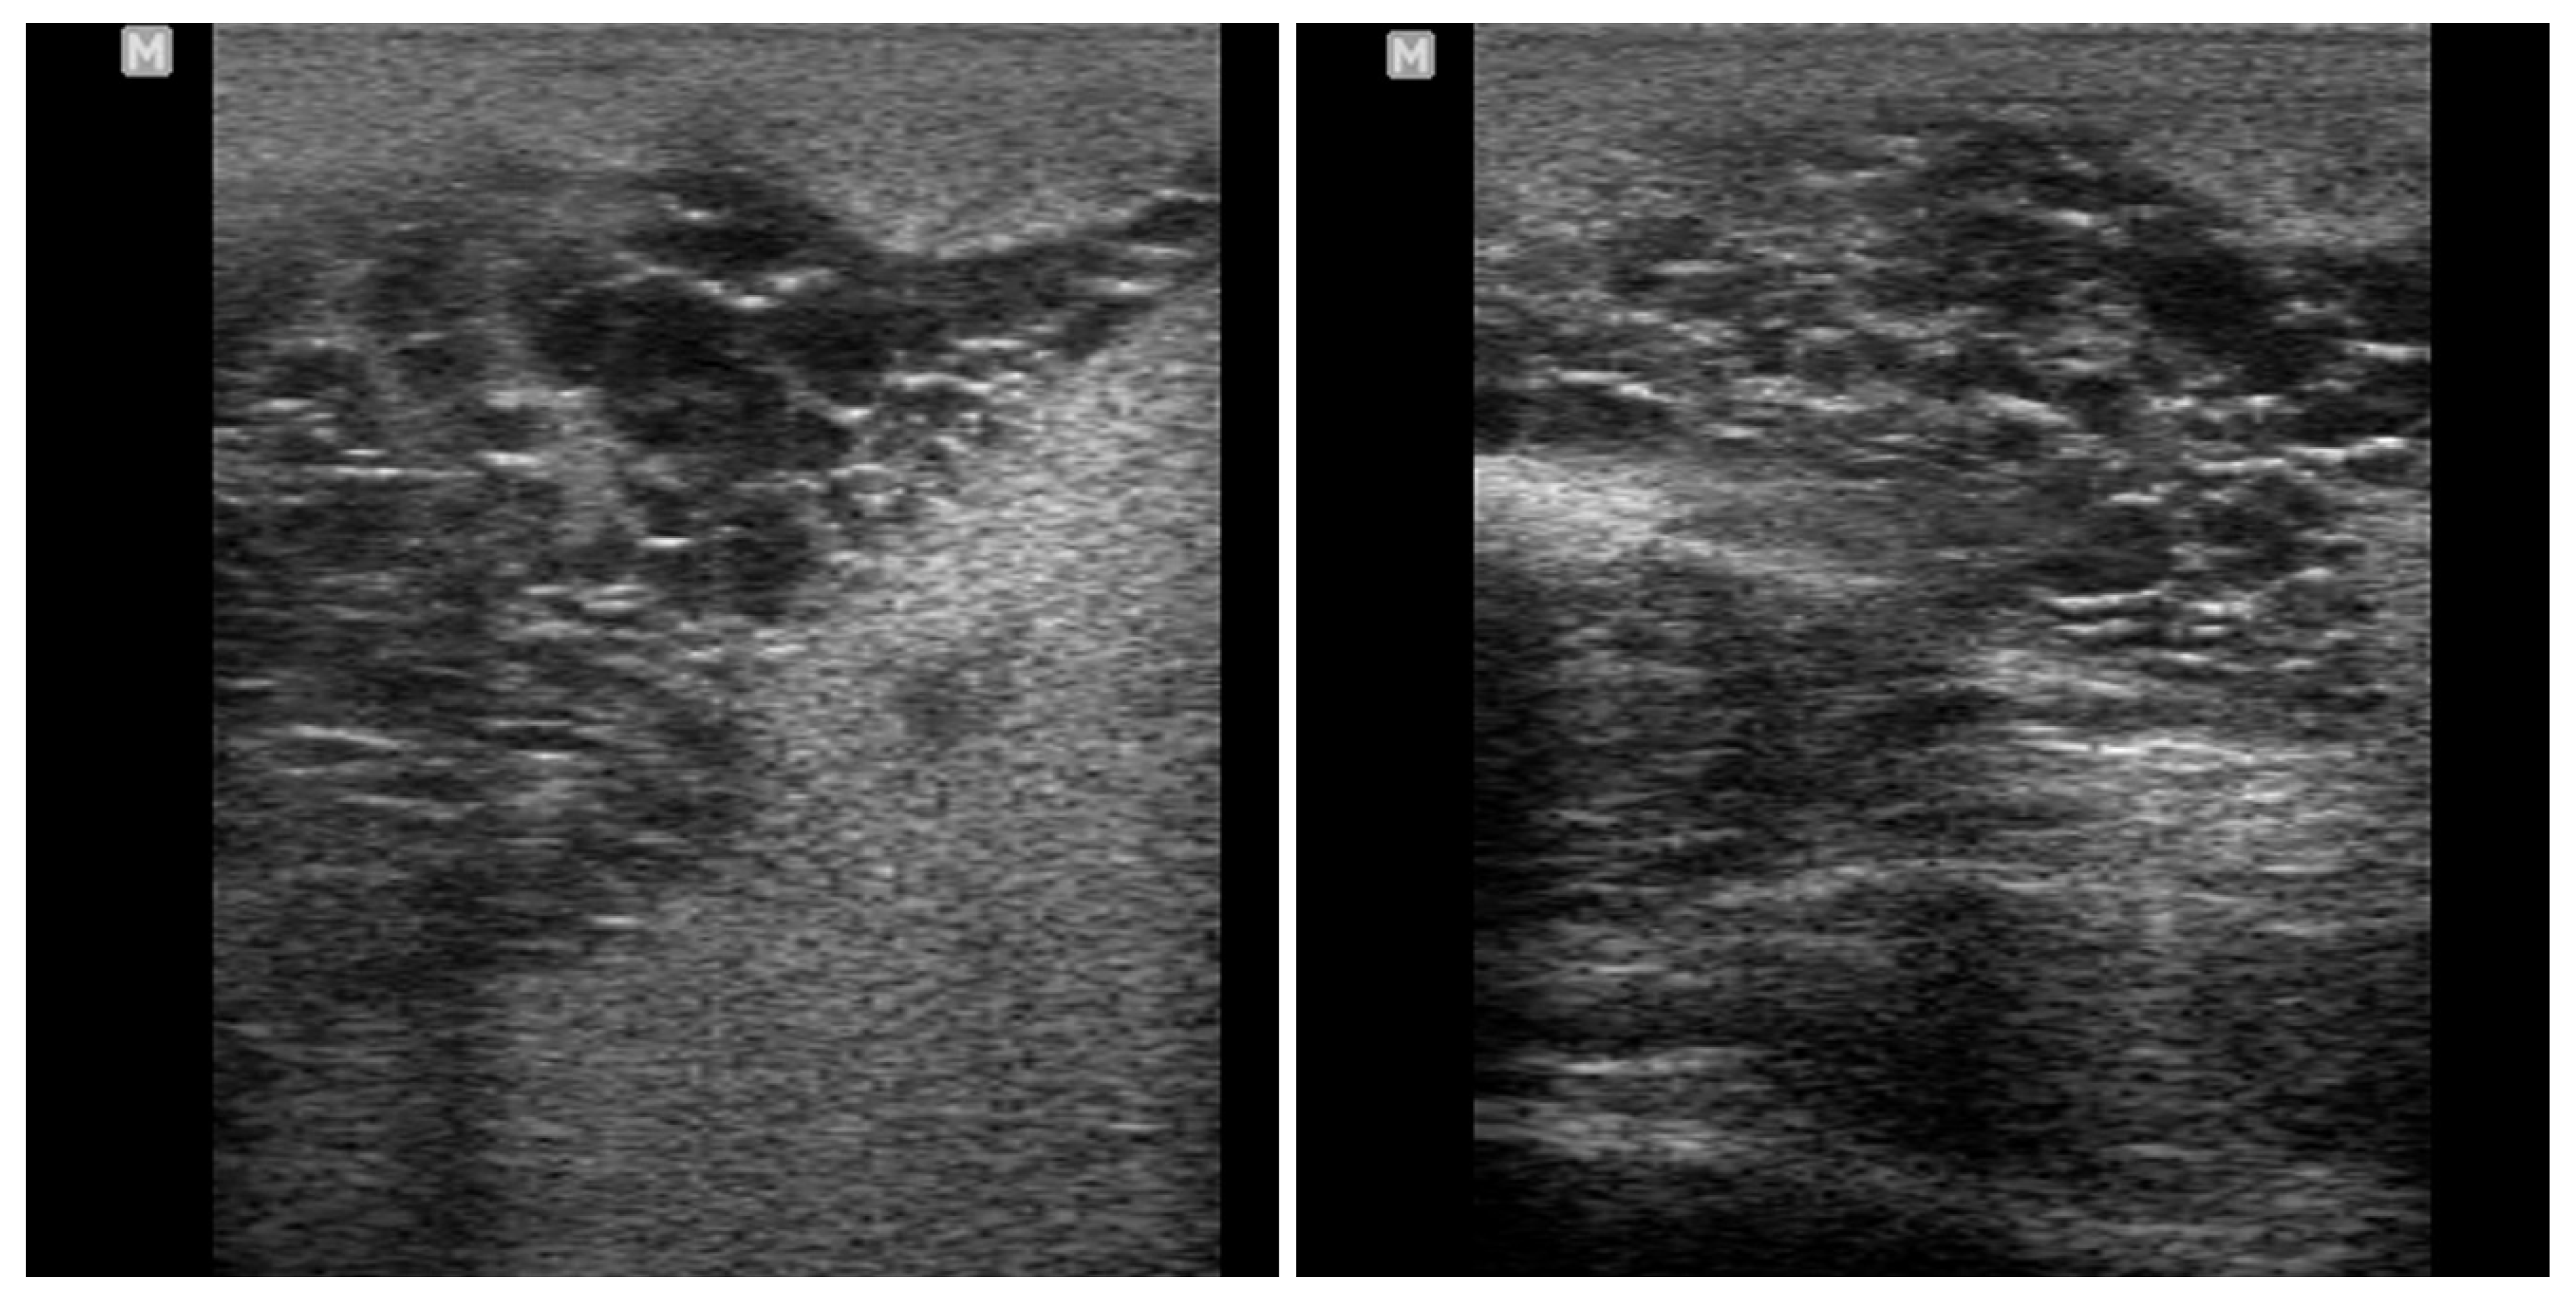

4.4. Orchitis and Epididymitis

5. Differential Diagnosis of Progressive Scrotal Enlargement